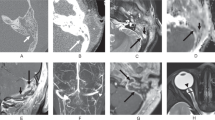

WB collected the data, designed the manuscript, prepared the first draft, figure, table, and panel. BBB, VB, and NJN designed the study, reviewed the data, prepared the manuscript, contributed to the discussion, critically edited the review, and approved its final version.